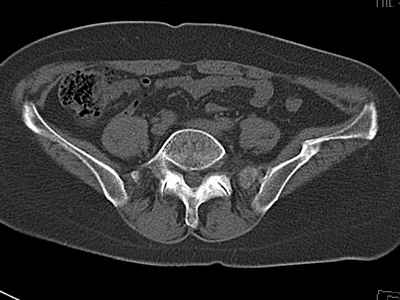

Уважаемые коллеги, возник вопрос по лечению нашей пациентки 60 лет. Около года назад множественная травма: в том числе Т-образный перелом вертлужной впадины. На сегодняшний день сращение отломков имеется на ограниченных участках, имеется дефект задней колонны вертлужной впадины. Движения неплохие, ходит с костылями, приступая на ногу. По мнению эдопротезистов при установке антипротрузионного кольца или октопуса не хватит костного материала и необходимо перед протезированием выполнить реконструкцию впадины, иначе чашка протеза неминуемо выпадет.Просьбы поделиться положительным и отрицательным опытом протезирования в подобных случаях.Возможно ли обойтись без реконструкции?Или лучше с ней?С уважением РАВ.

По моему мнению предварительну реконструкцию делать нет необходимости. Операцию надо выполнять одномоментно с пластикой вертлужной впадины. по поводу того, что не хватит головки. Да не исключено. Но ведь есть и другие материалы. Лучше при таком раскладе иметь в запасе замороженную головку. если нет возможности, как вариант два крыла подвздоной кости + хронос или его аналоги. По поводу выбора конструкции. Октопус в данной ситуации будет совсем не уместен, т.к. имеется дефект задней колонны вертлужной впадины. Да как конструкция октопус встанет не плохо. Но в функциональном плане не будет хорошей задне латерально и заднемедиальной точек опры впадины на период перестройки трансплатов. И по этому в данной ситуации более уместно кольцо Бурх(г)-Шнайдера с аналогичной пластикой, но возможнотью зафиксировать отломки задней колонны, крыши. Естественно цементная чашка с козырьком из кросс линк полиэтилена. Гололвка керамика, ножка бесцементная можно Цваймюллера или любой другой конструкции, они сейчас все хороши.

Октопус для того и существует, чтобы в подобных случаях обойтись одноэтапной операцией. Пластического материала вполне хватит - целая

головка. Для того, чтобы обеспечить достаточную антеверсию чашки - следует произвести экономную моделирующую резекцию передней колонны, чтобы несколько опустить передний край кольца и чашки - этот прием значительно уменьшает объем полости на месте вертлужной впадины.